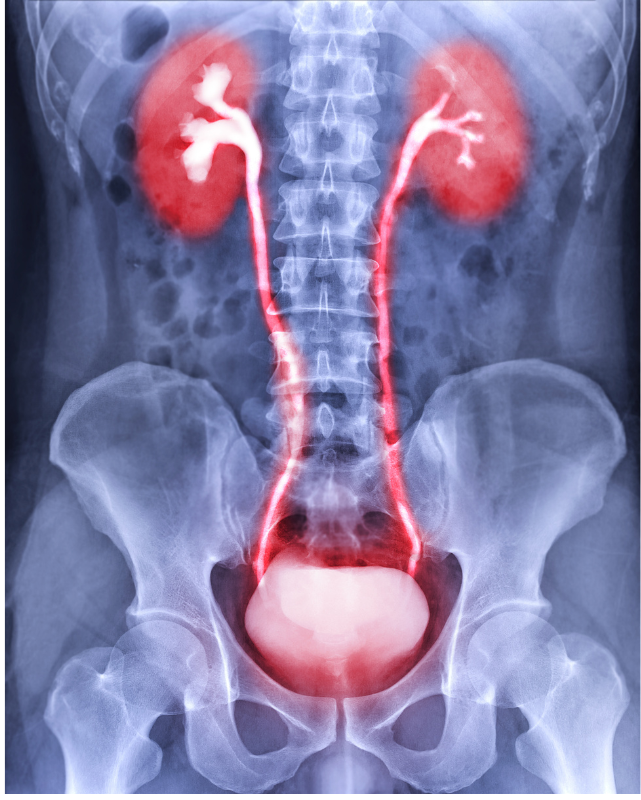

TURBT – ראשי תיבות של Transurethral Resection of Bladder Tumor – הוא הליך אנדוסקופי המתבצע דרך השופכה (ללא צורך בחתכים), ומטרתו להסיר גידול שהתפתח על רירית כיס השתן. זהו הטיפול שיאבחן מהות ממצא שהתגלה או בבדיקות הדמיה או בבדיקת ציסטוסקופיה המבוצעת לבירור סימני דם חדשים בבדיקת שתן, ופעולה זו היא גם אבחנתית וגם טיפולית.

TURBT הוא הליך אנדוסקופי זעיר-פולשני שבו הגישה לגידול נעשית דרך השופכה, ללא צורך בפתיחת הבטן או ביצירת חתכים בעור. הרופא משתמש בציסטוסקופ מיוחד המצויד במצלמה ובמערכת חיתוך חשמלית (loop resection), המאפשרת הסרה מדויקת של הגידול מהדופן הפנימית של השלפוחית.